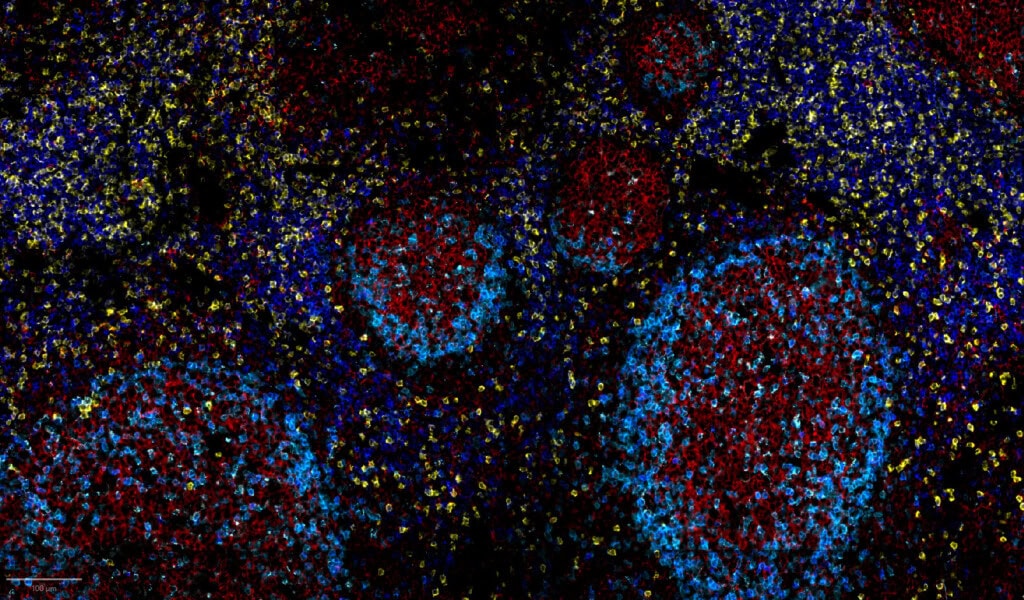

High-resolution imaging for precise single-cell phenotyping across complex tissues

CellScape PSP delivers market-leading spatial proteomics, capturing the widest dynamic range of protein expression per cell while maintaining single-cell resolution across complex tissues. This high-resolution, high- dynamic-range imaging ensures accurate detection of low-, mid-, and high-expressing biomarkers, enabling confident single-cell phenotyping and robust quantitative insights

FFPE Breast Cancer

HDR Composite